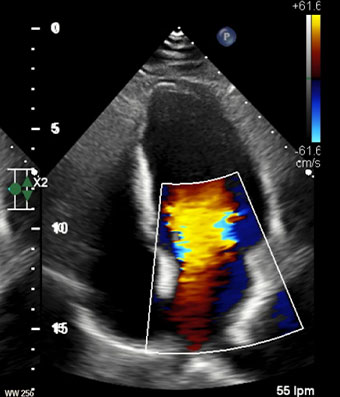

Ecocardiografía

El ecocardiograma o ecocardiografía utiliza ondas sonoras de alta frecuencia para obtener imágenes del corazón en vivo y que son proyectadas en una pantalla. Este auxiliar diagnóstico aporta información en 30 a 60 minutos de la forma, tamaño, función y movimiento del corazón así como de sus estructuras internas, como por ejemplo las válvulas cardiacas. Este estudio es seguro en pacientes adultos, en pacientes pediátricos (ecocardiograma pediátrico) o incluso en mujeres embazadas para estudiar el desarrollo del corazón del bebé en la cavidad uterina (ecocardiografía fetal).

Las imágenes ecocardiografías del corazón pueden ser obtenidas en diferentes modos (unidimensional, bidimensional o tridimensional, Doppler, Doppler color), utilizando una sonda externa (ecocardiograma transtorácico) o una sonda interna (ecocardiograma transesofágico) y puede ser adquirido en reposo, en estrés con esfuerzo físico o con el uso de medicamentos (estrés con dobutamina), dependiendo del diagnóstico y de la indicación de tú médico.